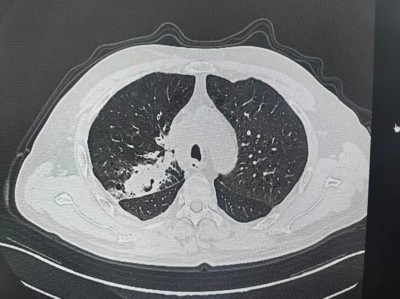

张大叔第一疗程治疗前后对比

治疗前

治疗第一个疗程后

2026年1月下旬,第一疗程顺利结束,复查影像显示:肿瘤较治疗前明显缩小,咳嗽频率减少,未出现咯血症状。